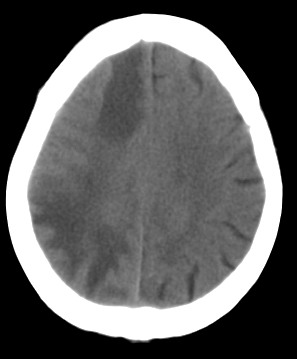

周*,女,78岁,阵发性意识障碍月余,查体四肢肌张力可,病理反射未引出。有脑哽塞病史

右颞顶枕叶多发低密度影,同侧脑室受压变形,病变有明显占位效应.考虑脑肿瘤性病变,建议增强!!!

影像表现: 右侧额、颞、顶叶多发等、低密度区,部分呈结节灶,灶周有不同程度水肿,散在发生,占位效应较重,感觉不是一个整体性病灶,病灶形态呈不规则状明显不同于mca供血区梗死,病变累及基底节区白质。

诊断:右侧额、颞、顶叶肿瘤性病变,首先考虑转移瘤。建议胸片。需与胶质瘤、mca供血区梗死以及脱髓鞘改变区别。

右侧颞,顶叶水肿呈指状,右额叶可见条形低密度带,右侧脑室明显受压,支持右侧脑实质多发转移瘤,建议增强,或拍胸部x片。

右颞顶枕叶多发低密度影,同侧脑室受压变形,病变有明显占位效应,建议增强.

病灶周围脑实质受压明显,右侧脑室受压变形,脑沟明显变浅。支持脑内肿瘤的第一诊断,(不知病人曾经的脑梗塞是否诊断明确),其次考虑脑梗塞的诊断(看起来不大像)

病史:女,78岁,阵发性意识障碍月余,查体四肢肌张力可,病理反射未引出。可基本除外缺血性病变。[br]影像表现: 右侧额、颞、顶叶多发等、低密度区,部分呈结节灶,灶周有不同程度水肿,散在发生,占位效应较重,感觉不是一个整体性病灶,病灶形态呈不规则状明显不同于mca供血区梗死,病变累及基底节区白质。[br]诊断:右侧额、颞、顶叶肿瘤性病变,首先考虑转移瘤。建议胸片。需与胶质瘤、mca供血区梗死以及脱髓鞘改变区别。

右侧额叶大片状水肿,呈指状改变,周围脑沟脑裂消失,右侧脑室受压缩小,提示占位效应明显,平扫未见明显瘤体,单纯从ct片上看可考虑肿瘤,转移瘤或胶质瘤,建议mri检查,以明确诊断.

右侧额、颞、顶叶多发不同程度低密度水肿区,可见占位效应

首先考虑右侧额、颞、顶叶肿瘤性病变,转移瘤可能性大。(部分病灶可能是梗塞性改变)